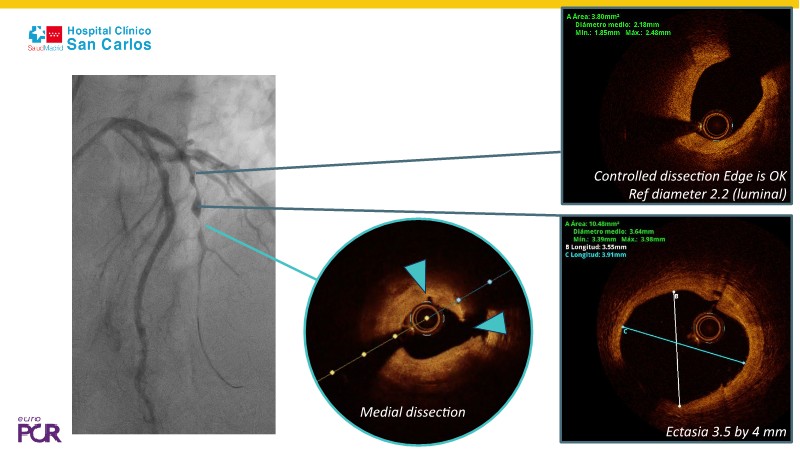

Discover how the next-generation RevoEdge high-pressure cutting balloon is transforming PCI with innovative design and proven clinical outcomes. This session presents a multicenter randomised trial and real-world case discussions, showcasing RevoEdge’s effectiveness in tackling resistant, complex lesions—including long, tortuous, and fibrotic cases. Learn practical tips, tricks, and intravascular imaging insights to optimize lesion preparation and improve patient outcomes. Don’t miss this opportunity to see how RevoEdge helps you cut through challenges and conquer PCI complexities.

- To learn about the clinical benefits and tips and tricks of using RevoEdge high pressure cutting balloon in different types of complex lesions through case-based discussion